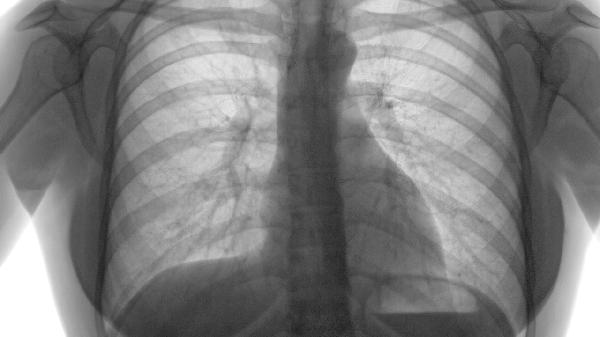

肺气肿能治吗?最新治疗方案全解析

肺气肿的治疗方式包括药物、吸氧、康复训练、手术以及生活方式的调整。这种疾病通常由长期吸烟、空气污染、遗传因素、职业性粉尘接触和反复的呼吸道感染等引起。